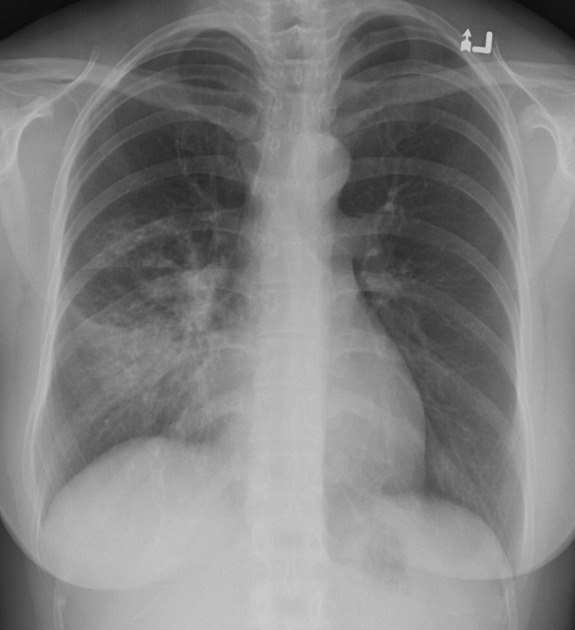

Describe the abnormality demonstrated.

Consolidation of the right middle lobe, with obscuration of the right cardiac border and right cardiophrenic recess (positive silhouette sign) and air bronchograms.